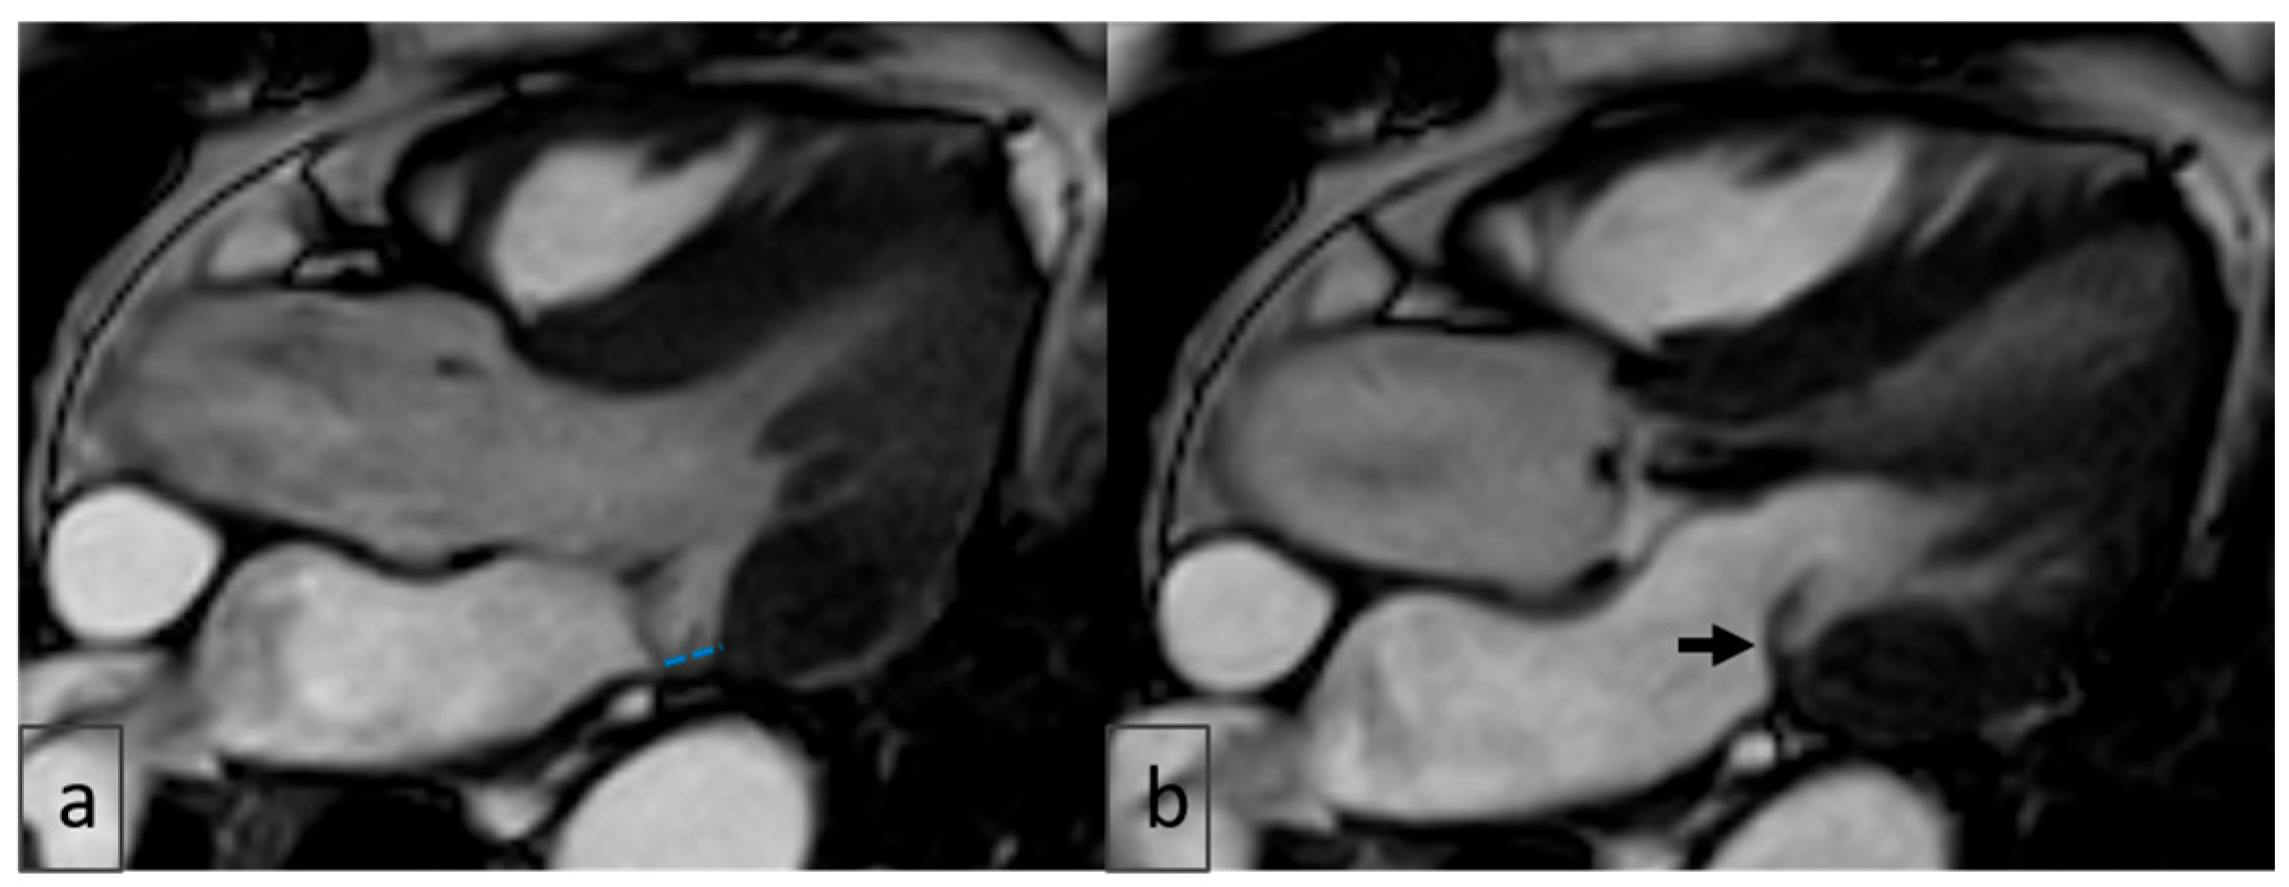

2.4. Image Analysis